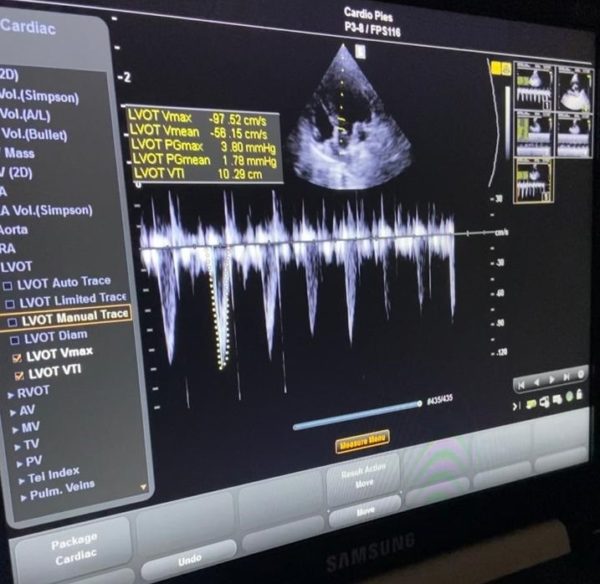

Tapse Echo Serca The tricuspid annulus plane systolic excursion (tapse) and tricuspid regurgitation peak gradient (trpg) can be used. The tricuspid annulus plane systolic excursion (tapse) and tricuspid regurgitation peak gradient (trpg) can be used. The ratio of tricuspid annular plane systolic excursion (tapse) to echocardiographically measured systolic pulmonary artery pressure (pasp) has been. Found a statistically significant relationship between lower values of tapse, assessed by echocardiography, and rvef, assessed by mri. On the other hand, koestenberger et al. Tricuspid annular plane systolic excursion (tapse) is an established echocardiographic marker of right ventricular. Decreasing rv systolic function, assessed as tapse, was a univariable predictor of cvd (hazard ratio, 1.13;